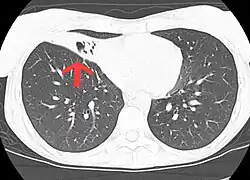

| CT scan of patient with right middle lobe aspiration and Mycobacterium avium infection. | |

MAC usually affects patients with abnormal lungs or bronchi. However, Jerome Reich and Richard Johnson describe a series of six patients with MAC infection of the right middle lobe or lingula who did not have any predisposing lung disorders.[17][18]

The right middle lobe and lingula of the lungs are served by bronchi that are oriented downward when a person is in the upright position. As a result, these areas of the lung may be more dependent upon vigorous voluntary expectoration (cough) for clearance of bacteria and secretions.

- Chest X-ray or CT scan showing evidence of right middle lobe (or left lingular lobe) lung infection